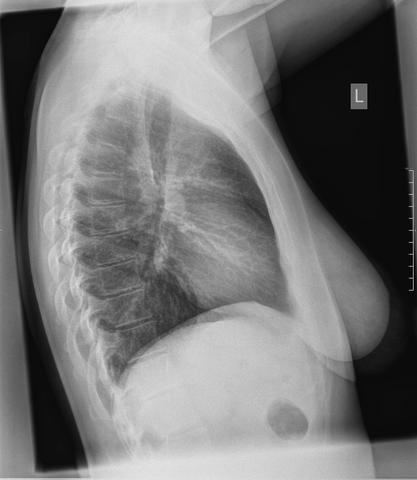

Bei einer Lungenembolie wird ein Blutgerinnsel in eine Lungenarterie eingeschwemmt und kann diese so verstopfen. So gelangt nur unzureichend Sauerstoff ins Blut. Kleine Embolien vergehen oft symptomlos Verschlüsse großer Lungengefäße können im schwersten Falle einen Herz-Kreislauf-Stillstand bewirken.

Bei einer Lungenembolie auch Lungenarterienembolie genannt ist eine Arterie der Lunge durch ein Blutgerinnsel verstopft. Ein typischer Vormittag in der Praxis.

Lungenembolie Anzeichen können je nach Patient und Schwere des Arterienverschlusses variieren.

Lungenembolie Anzeichen können je nach Patient und Schwere des Arterienverschlusses variieren. Ein besonders hohes Thromboserisiko haben bettlägerige Menschen frisch Operierte. In der Folge fällt der Blutdruck ab die Organe werden nicht mehr richtig durchblutet und dem Körper fehlt Sauerstoff. Sind die blutzuführenden Gefäße der Lunge verstopft kann dies eine Lungenembolie auslösen. Bei Herzinfarkt und Schlaganfall verstopft ein Blutgerinnsel ein lebenswichtiges Gefäß im Herzen oder im Gehirn. Bei einer Lungenembolie wird ein Blutgerinnsel in eine Lungenarterie eingeschwemmt und kann diese so verstopfen. Mit dem Blut wurde es anschließend in die Lunge geschwemmt.